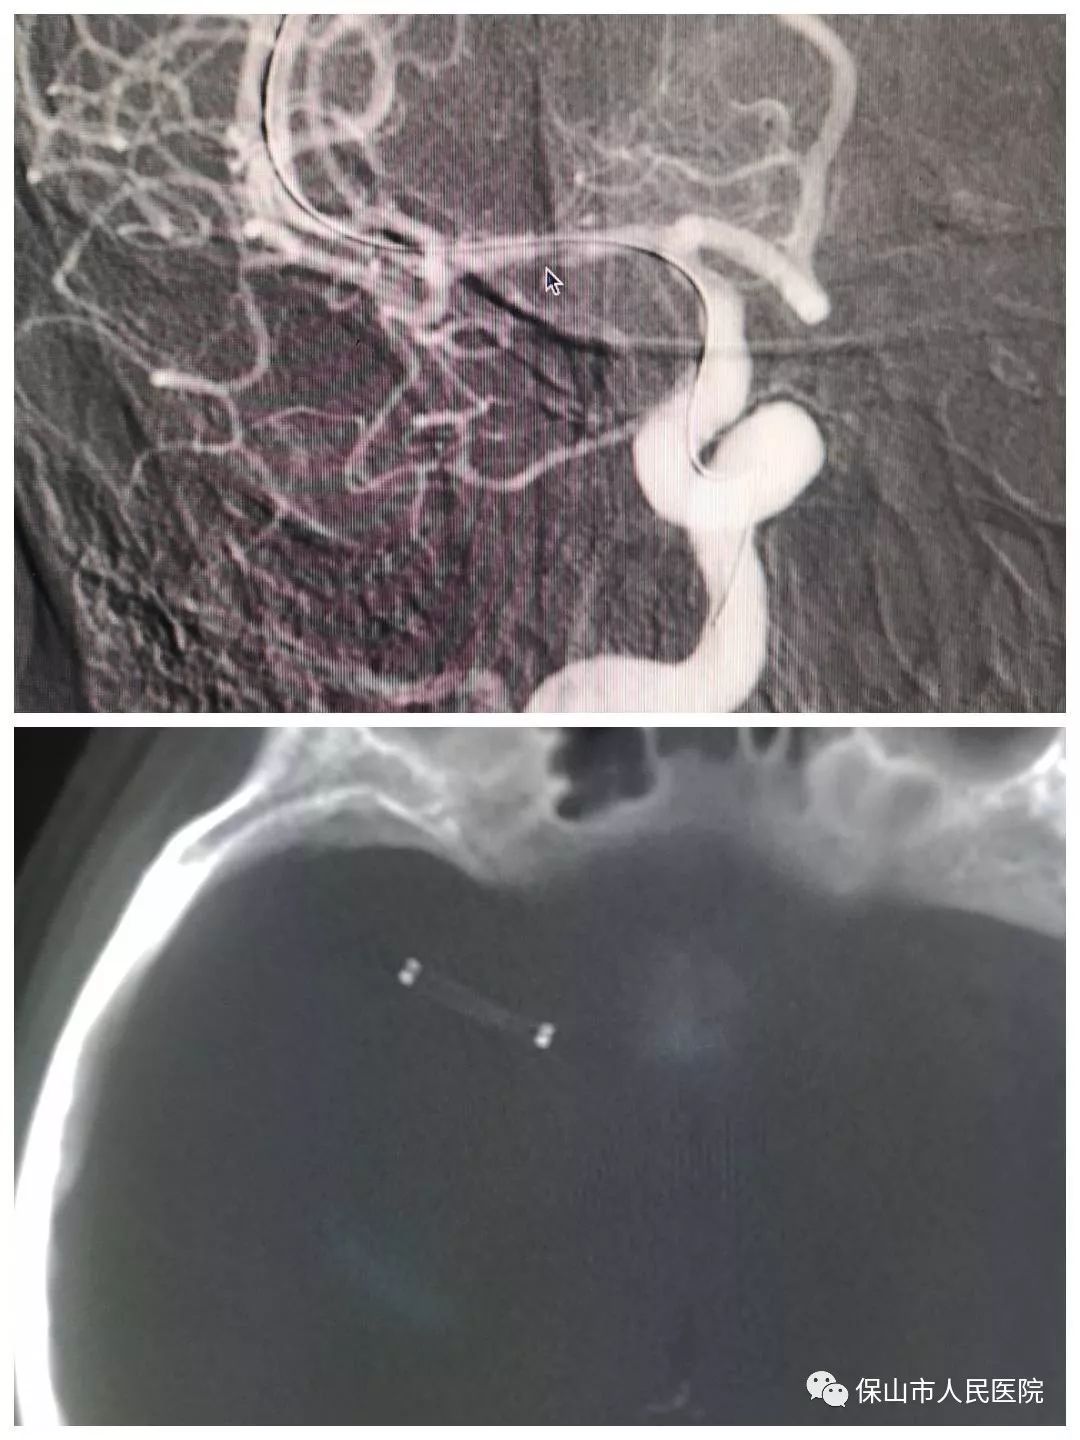

接下來一名女性患者,49歲,於(yu) 6月10日突發左側(ce) 肢體(ti) 活動障礙,口齒不清。入院做了核磁共振(MRI)和CT檢查,考慮右側(ce) 大腦中動脈梗塞,由於(yu) 多方麵因素,到達醫院已經過了溶栓和急診取栓時間。隻能暫時內(nei) 科保守治療,目前病情趨於(yu) 平穩,家屬要求進一步治療,於(yu) 6月20日進行支架植入術。

術中造影如上圖所示,箭頭標注的地方就是右側(ce) 大腦中動脈狹窄的部位,可以看到,狹窄程度大約在60%左右,雖然經過內(nei) 科治療後血流可以通過狹窄部位,但是狹窄部位後麵血管的血流速度較慢,大腦作為(wei) 需要大量血液快速交換的器官,患者右側(ce) 大腦半球的供血情況明顯是不理想的,而且患者隨時存在再次發生腦梗塞的風險,所以有必要進行支架植入術。

同樣的方法,通過導管和導絲(si) 的配合,將支架送到右側(ce) 大腦中動脈狹窄部位,確認好狹窄部位的位置後,釋放支架。

支架植入完成後,再次造影,可以看到,不僅(jin) 狹窄部位支撐開了,而且狹窄部位後麵的血管裏的血流速度也比手術前增加了。狹窄部位撐開,血流速度恢複,兩(liang) 個(ge) 條件都滿足了,手術也就圓滿結束了。